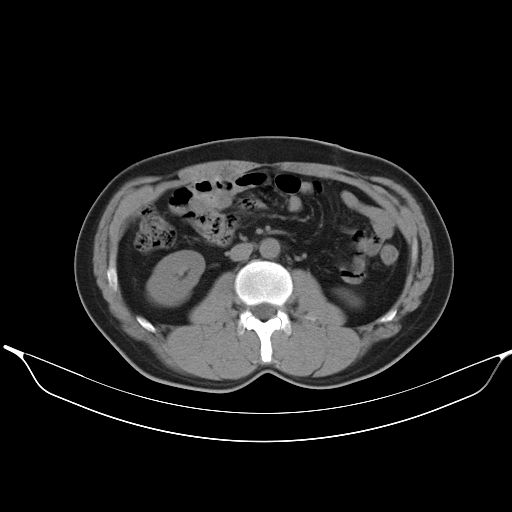

标题: CT25490:男,40岁,体检发现;无其它不适。 [打印本页]

标题: CT25490:男,40岁,体检发现;无其它不适。

转移性肺肿瘤不排除,建议结合相关检查考虑

考虑右下肺周围性肺癌并肺内多发转移,纵隔淋巴结转移!

支持 !考虑右下肺周围性肺癌并肺内多发转移,纵隔淋巴结转移,(气管前腔静脉后,隆突下,主动脉弓下都有了)

1、均为转移,原发灶不在肺内。2、肺癌肺转移。